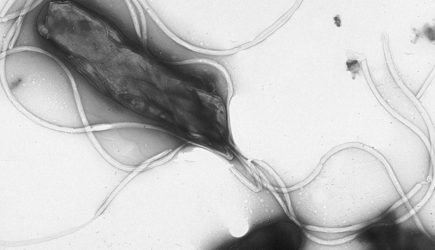

Фото: Yutaka Tsutsumi, M.D. Professor Department of Pathology Fujita Health University School of Medicine / Wikimedia

По словам врача, часто к раку желудка приводят воспаления слизистой оболочки этого органа. «Наиболее изученным фактором риска является инфекция Helicobacter pylori, которая может приводить к формированию атрофического гастрита, кишечной метаплазии и другим предраковым изменениям», — предупредил Бамматов.